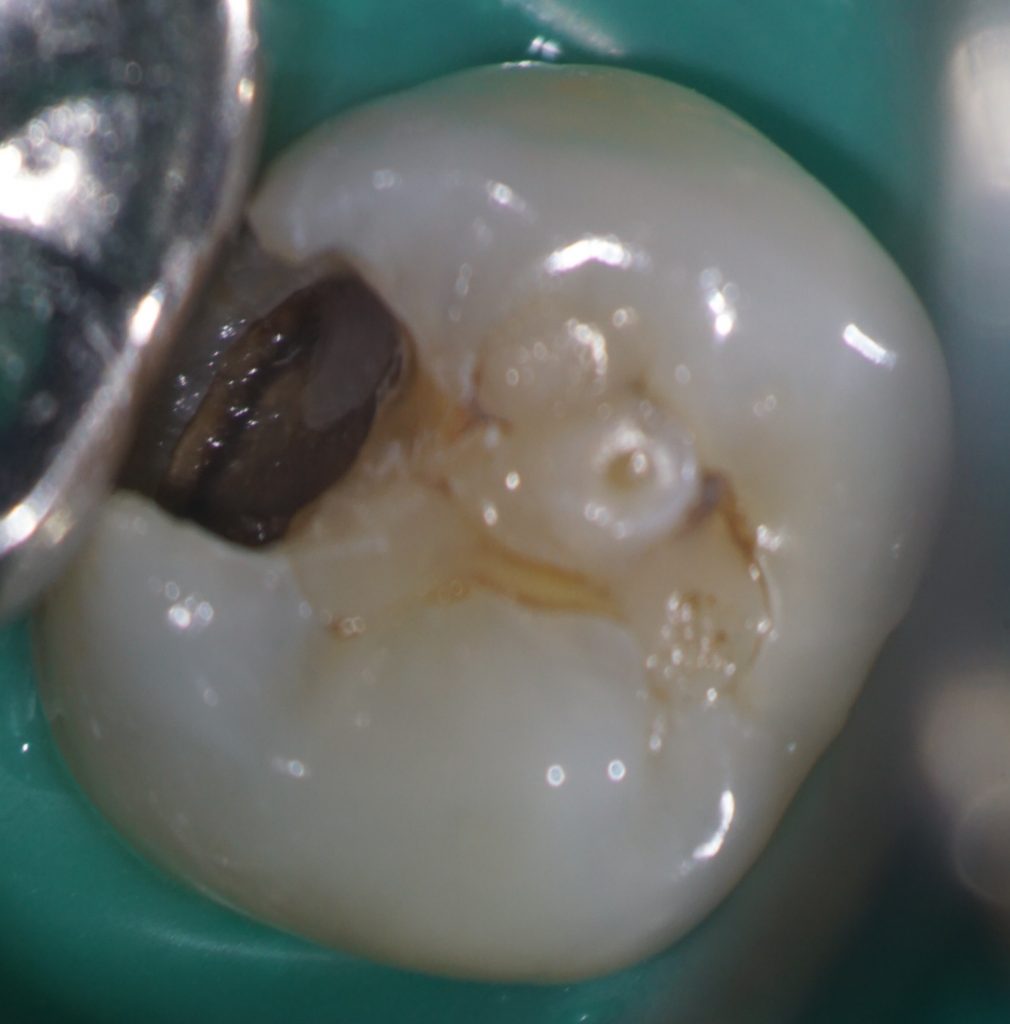

たとえば、この症例はいかがでしょう。

中心結節がある症例では、中心結節に歯髄が嵌入していることが知られています。

この症例を普通に治そうとするとインレーになりますよね。

しかし、通法の形成ではイスムスを形成しているときに露髄してしまうかもしれません。

私はこういった症例の治療をする場合、う蝕を取り除き、

露髄していないことを確認したうえで、コンポジットレジンで修復することがほとんどです。

これを自由診療で行っています。

患者さんは、歯髄を失わなくて済むので自由診療を選択したことをとても喜んでくれます。